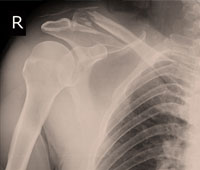

8.What is frozen shoulder and how is it caused?

Frozen shoulder refers to a condition where the shoulder seems to be frozen in its movements. This condition cause pain and stiffness in the shoulder and restricts any kinds of movements. Medically, this condition in also known as adhesive capsulitis.

While the exact cause of frozen shoulder is not understood, it is believed to be caused due to a swelling of the joints covering called as capsule. This may happen due to long periods of immobility or trauma to the underlying nerve.